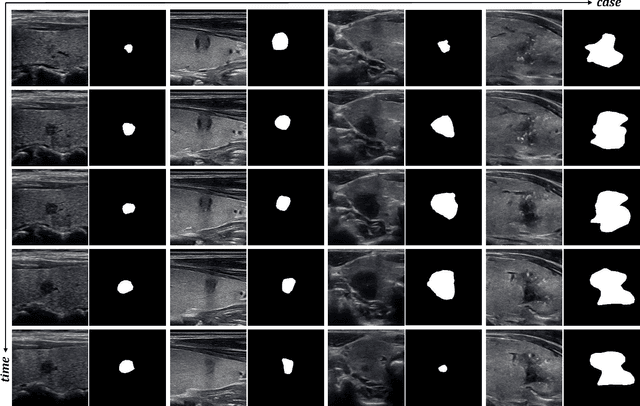

Traditional convolutional neural networks have a limited receptive field while transformer-based networks are mediocre in constructing long-term dependency from the perspective of computational complexity. Such the bottleneck poses a significant challenge when processing long video sequences in video analysis tasks. Very recently, the state space models (SSMs) with efficient hardware-aware designs, famous by Mamba, have exhibited impressive achievements in long sequence modeling, which facilitates the development of deep neural networks on many vision tasks. To better capture available cues in video frames, this paper presents a generic Video Vision Mamba-based framework for medical video object segmentation tasks, named Vivim. Our Vivim can effectively compress the long-term spatiotemporal representation into sequences at varying scales by our designed Temporal Mamba Block. Compared to existing video-level Transformer-based methods, our model maintains excellent segmentation results with better speed performance. Extensive experiments on breast lesion segmentation in ultrasound videos and polyp segmentation in colonoscopy videos demonstrate the effectiveness and efficiency of our Vivim. The code is available at: https://github.com/scott-yjyang/Vivim.